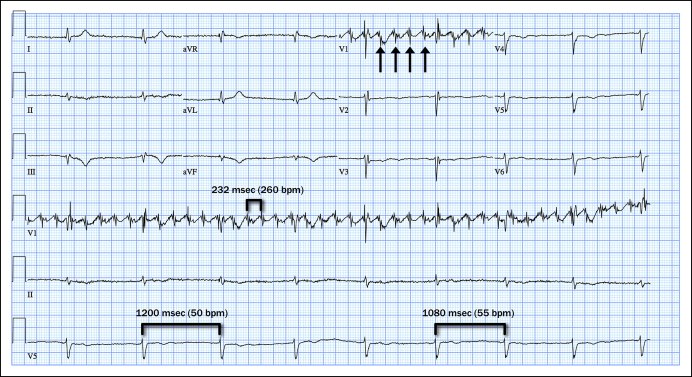

Atrial Flutter EKG

Atrial Fibrillation classification

Junctional Rhythm

Преждевременное сердцебиение

Тахикардия на ЭКГ фото

Определение пейсмейкера в ЭКГ это

Кардиостимулятор DDR на ЭКГ

Брадикардия фибрилляция предсердий на ЭКГ

Ventricular Fusion Beat

Наджелудочковая аберрантная тахикардия